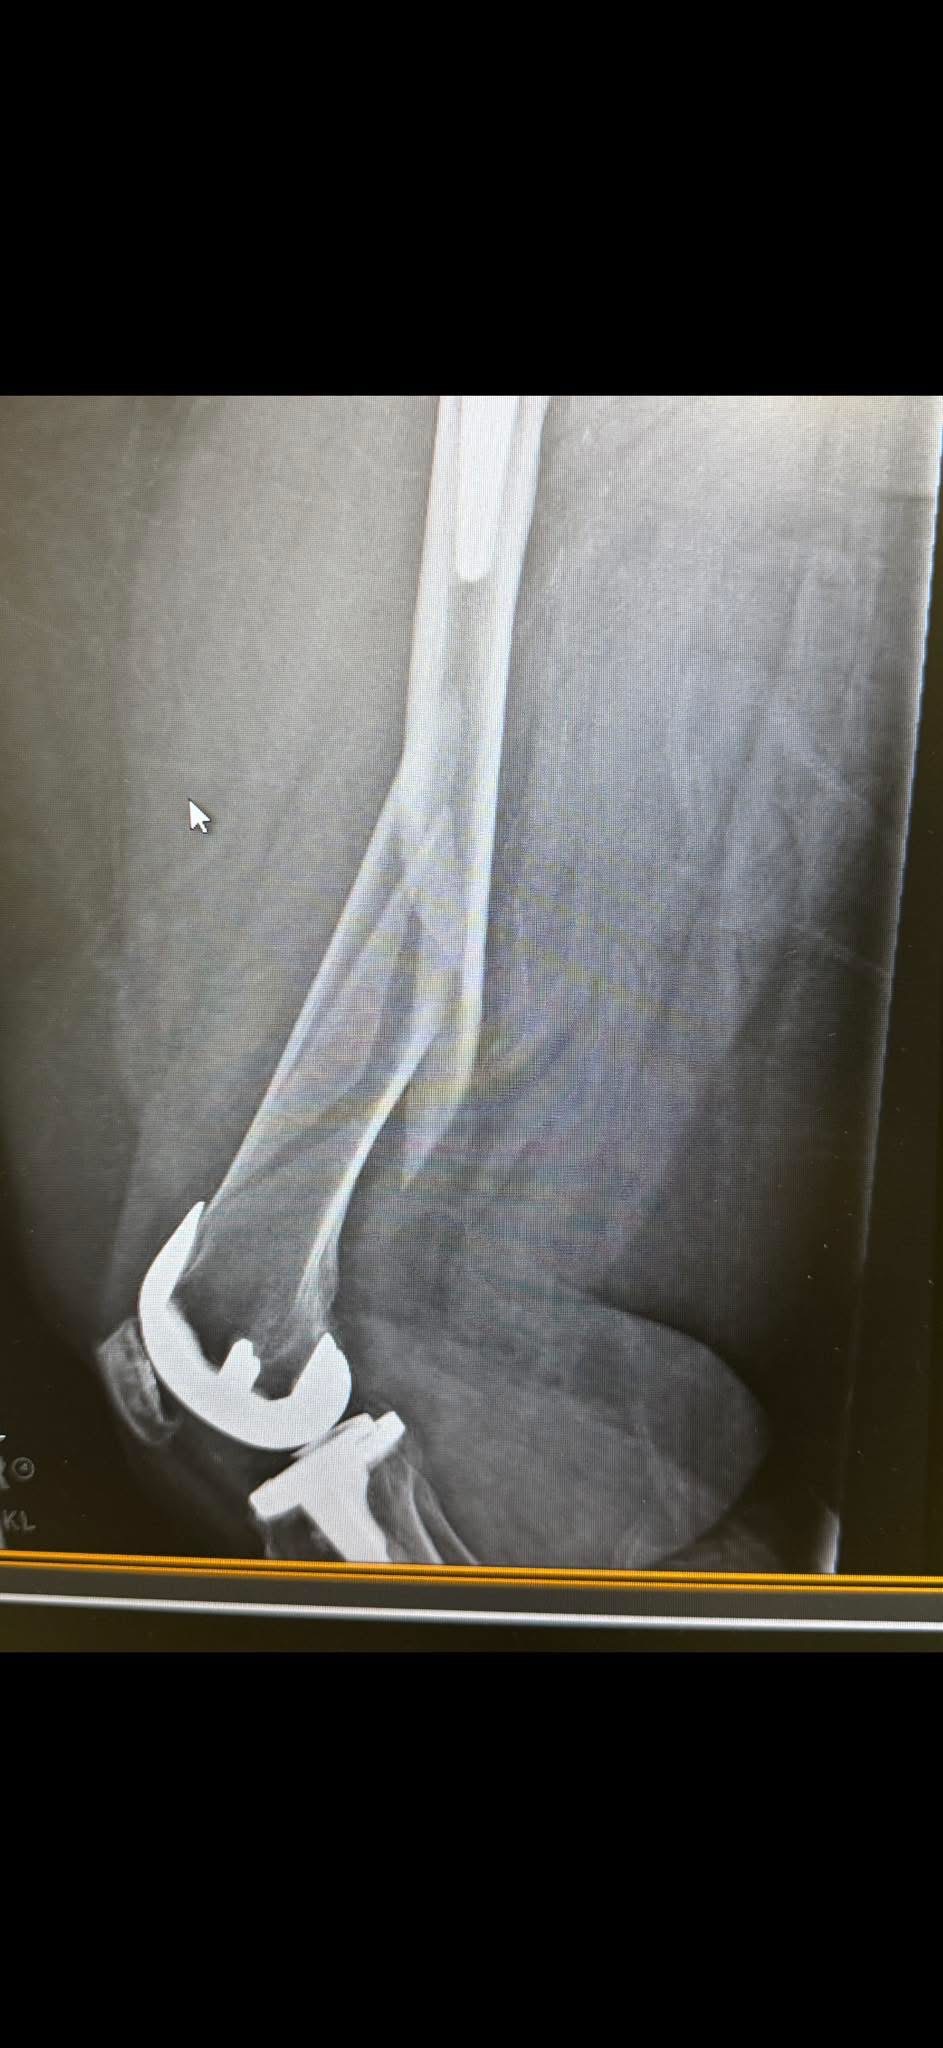

I never thought I would be in a position to have to ask for help, but I recently fell on December 9th and broke my femur, requiring immediate surgery to repair it. Since then, I have gone from the hospital to a rehab facility to get my strength back.